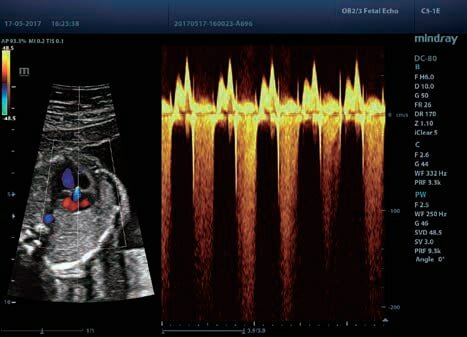

Клинические изображения

B, M, CFM, цветной М-режим, PDI и Dir.PDI, а также комбинированные режимы B+M, PW+B, Color+B, Power+B, PW+Color+B, Power+PW+B

- Комплексное кардиологическое исследование – диагностика сердца по одной или нескольким M-линиям одновременно, тканевая допплерография и оценка деформации миокарда при помощи режимов Free Xros M, TDI и Tissue Tracking.

Базовые режимы сканирования: B, M, CFM, цветной М-режим, PDI и Dir.PDI, а также комбинированные режимы B+M, PW+B, Color+B, Power+B, PW+Color+B, Power+PW+B

Функции ультразвукового аппарата Mindray DC-80 X-Insight: PSH, iBeam, iClear, iTouch, iWorks, iNeedle iZoom, iScanHelper, Echo Boost, HR Flow, Depth VR, Smart Track, Smart3D, 4D, Smart-V, Auto IMT, Auto EF, Free Xros M, Free Xros CM, STIC, Color 3D, Stress Echo, TDI, TDI QA, Niche, iLive, iScae View, STE, STQ, MedTouch, компрессионная эластография, эластография сдвиговой волны, контрастные исследования и другие.